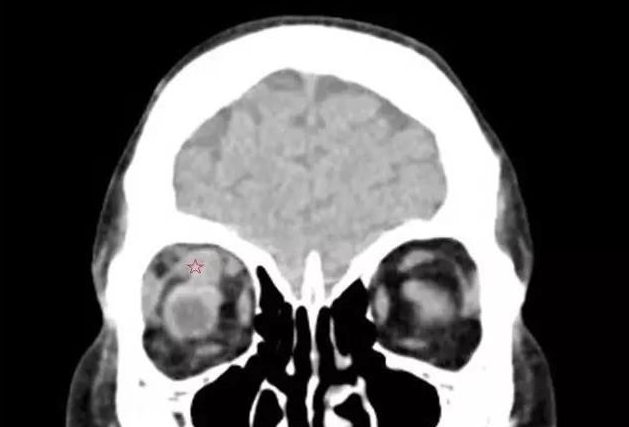

甲状腺相关眼病,是眼科较常见的疾病之一 。其包括:眼球突出、复视等,对患者的生活和工作带来极大的不便。

谢仁艺副主任医师介绍,刘先生眼睛病变是因甲亢引起,导致双眼眼外肌发炎、肿胀、变性、纤维化, 终失去弹性,这也是他眼球转动不灵活引起斜视、复视的主要原因。